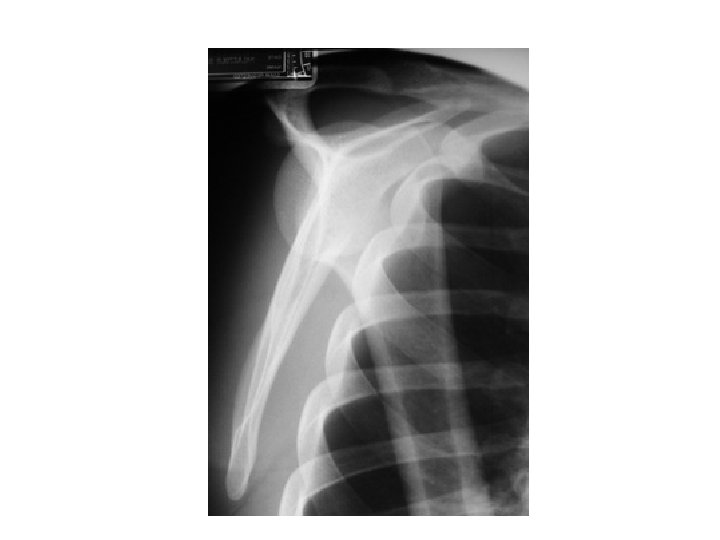

Post reduction

Bankhart

Complications of anterior glenohumeral dislocation and reduction • Neurovascular – neuropraxic and recover in days-weeks • Fractures – Hill-Sachs – 11 -50% of ant dislocations. May be higher if consider minor compression fractures – Bankart – ant glenoid rim #. 5% of cases. – Avulsion # of greater tuberosity in 10 -15%.